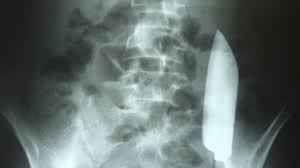

🕵️‍♂️ Radiologia Pericial

Essa área está ligada à medicina legal e é usada em investigações criminais e civis. O técnico pode atuar junto a peritos em casos de identificação de vítimas, análise de traumas incompatíveis com relatos, e reconstruções de cenas de crime.

O conhecimento técnico é essencial para garantir que as imagens sirvam como provas confiáveis no processo judicial.

O exame de raio-X utiliza radiação ionizante de alta energia que atravessa os tecidos do corpo e é absorvida de forma diferente conforme a densidade dos órgãos e estruturas. Os ossos, por exemplo, absorvem mais radiação e aparecem mais brancos, enquanto tecidos moles deixam passar mais radiação, formando tons mais escuros. Esse contraste é o que forma a imagem final.

É um método rápido, barato e amplamente utilizado em diagnósticos de fraturas, infecções pulmonares, dores articulares, entre outros. Apesar de seguro em baixas doses, seu uso em gestantes e crianças requer cautela, devido à sensibilidade à radiação.